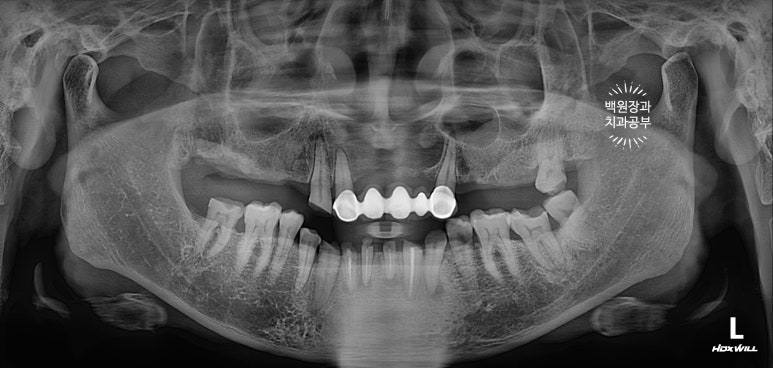

치과용 파노라마 엑스레이를 보시면 더 드라마틱한 변화를 느끼실 수 있어요.

다수의 치아가 씌워지고, 임플란트로 회복되어 마치 사이보그같은(?!) 느낌이 들긴 하지만,

정갈하게 치료가 잘 된 느낌입니다.!!!

임플란트의 위치가 적절히 배치되어 있어, 임플란트에서 크라운까지 이어지는 emergency profile이 예술이네요.

들쭉날쭉한 치아 없이 조화로운 교합이 형성되어 있는 것을 보실 수 있을거에요.

교합평면도 가지런하게 형성되어 보입니다.

위의 두 장의 사진이 저희 병원에 처음 내원하셨을 때의 사진입니다.

아래 두 장의 사진은 저희 병원에서 약 9개월간의 치료를 받으신 후의 결과이구요.

식사가 거의 불가했던 환자분이 어금니를 회복함으로 인해 양쪽으로 식사가 가능한 상태가 되셨고,

뿌리만 남아 기능적, 심미적으로 불량했던 아래 앞니는 임플란트 치료를 통해 올바른 길이와 모양으로 재탄생 하였습니다.